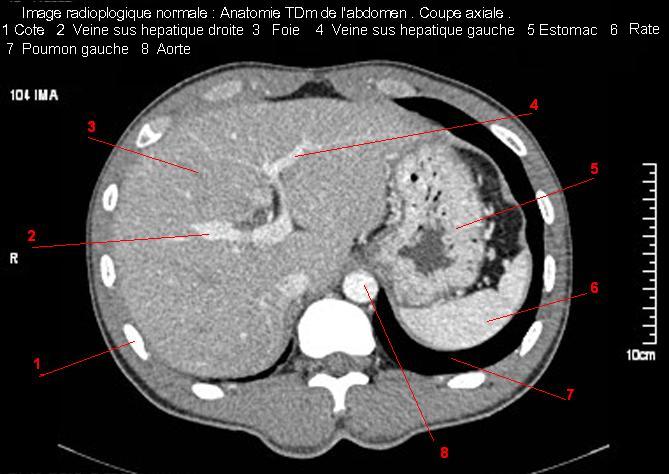

Image TDM

normale du foie :

Image TDM du foie avec

contrast intraveineuse . Coupe axiale a travers

tronc portale et vesicule biliaire . Double de click pour agrandir . |

|

tronc portale et vesicule biliaire et tronc

coeliaque . Double de click pour agrandir . |